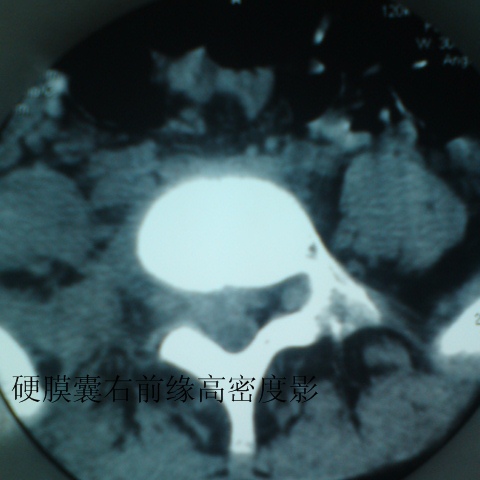

标题: CT27836:女 ,13岁,腰痛数月,加重一月,检查下腰部明显压 [打印本页]

标题: CT27836:女 ,13岁,腰痛数月,加重一月,检查下腰部明显压

考虑腰4椎体结核伴右侧椎旁及椎管右侧硬脊膜外脓肿形成。

考虑腰椎结核伴右侧椎旁及椎管右侧硬脊膜外寒性脓肿形成;建议必要时行mri检查。